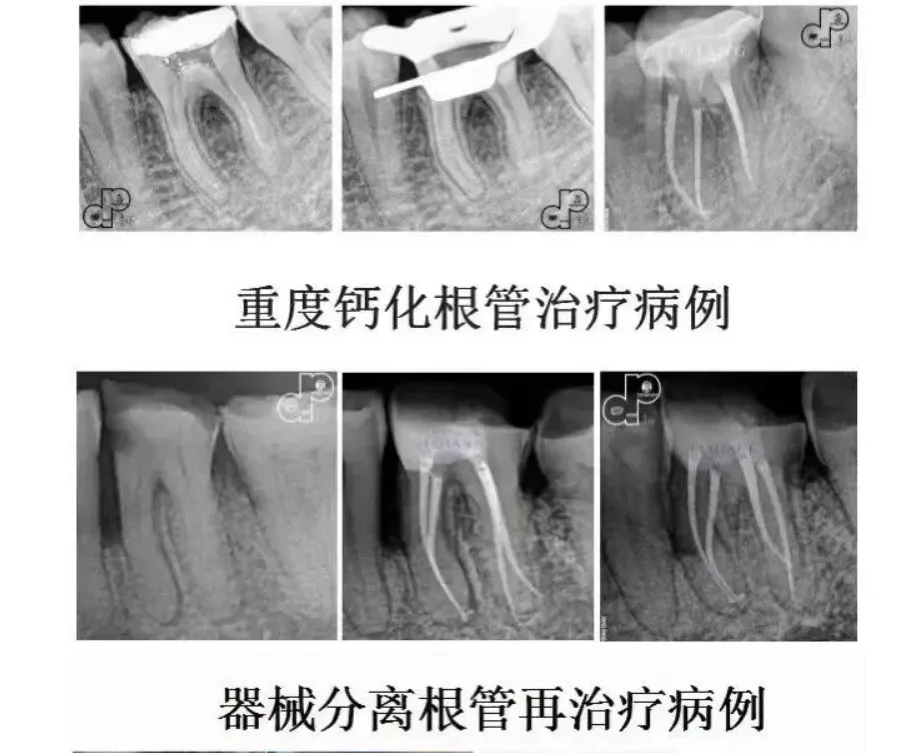

病例展示: